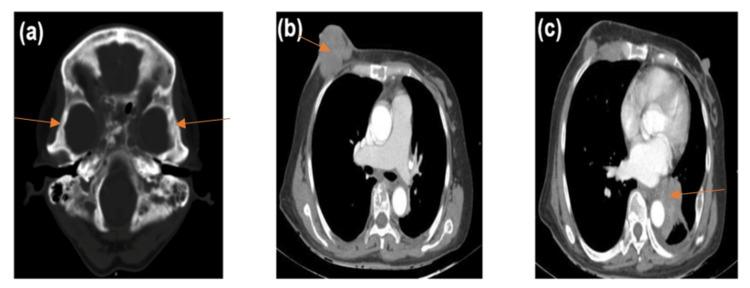

Isolated facial nerve palsy resulting from temporal bone metastasis is rare and has been sparsely reported in the literature to be the initial presentation of cancer. The most commonly reported sites of origin of such metastases include the breast, lung, kidney, gastrointestinal tract, larynx, prostate, and thyroid, to name a few. Here, we discuss a patient initially presenting with isolated lower motor neuron facial nerve palsy. The diagnosis was revised to that of breast cancer with metastasis to the temporal bone resulting in facial nerve paralysis following the subsequent clinical presentation.

由颞骨转移引起的孤立性面神经麻痹较为罕见,在文献中鲜有报道作为癌症的首发表现。此类转移最常报道的原发部位包括乳腺、肺、肾、胃肠道、喉、前列腺和甲状腺等。在此,我们讨论一名最初表现为孤立性下运动神经元面神经麻痹的患者。在随后的临床表现后,诊断修正为乳腺癌伴颞骨转移导致面神经麻痹。